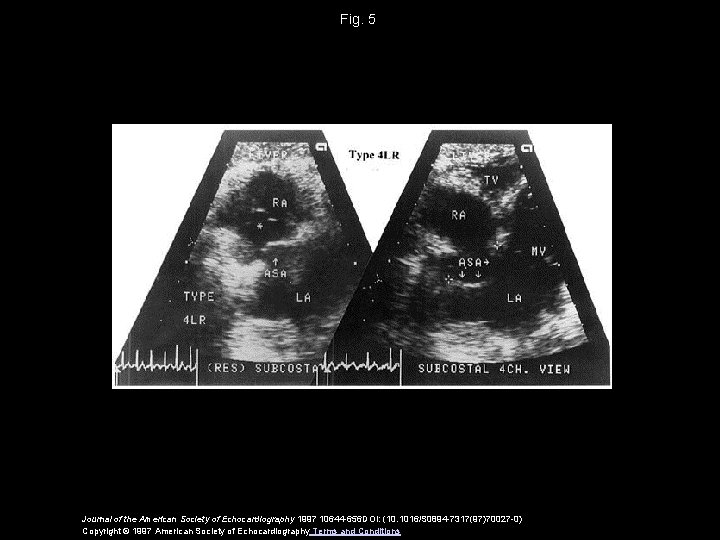

Fig. 5 Journal of the American Society of Echocardiography 1997 10644 -656 DOI: (10.

Fig. 5 Journal of the American Society of Echocardiography 1997 10644 -656 DOI: (10. 1016/S 0894 -7317(97)70027 -0) Copyright © 1997 American Society of Echocardiography Terms and Conditions